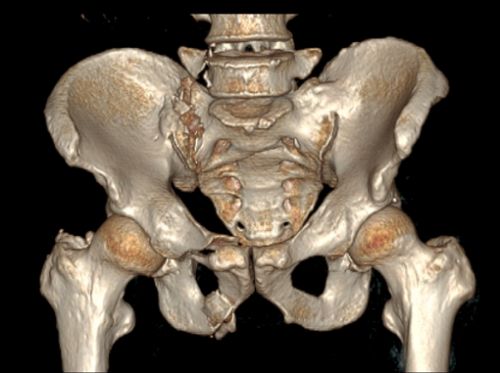

术前ct显示:骶骨骨折累及骶髂关节面。

入院检查发现,周先生骨盆、骶骨、骶髂关节面、腰2椎体、腰5椎体横突及肋骨共有6处骨折,同时出现肾包膜血肿形成、双肺挫伤、失血性贫血。如此严重的伤情必须尽快手术治疗,否则长期卧床会加重病情,甚至危及生命。

捷克论坛 岳麓山院区创伤骨病科主任盛斌反复阅片后认为,周先生的骨盆骨折是不稳定型骨折,手术难度大,如果采用常规的开放复位钢板内固定手术,手术伤口将长达2030cm,而且手术时间长,出血多,费用高,术后疼痛加重、恢复慢,伤口感染风险大;而采用骨盆微创经皮骶髂螺钉和Infix内固定手术,具有损伤小、费用低、固定稳定、恢复快等传统手术方法无法比拟的优势。